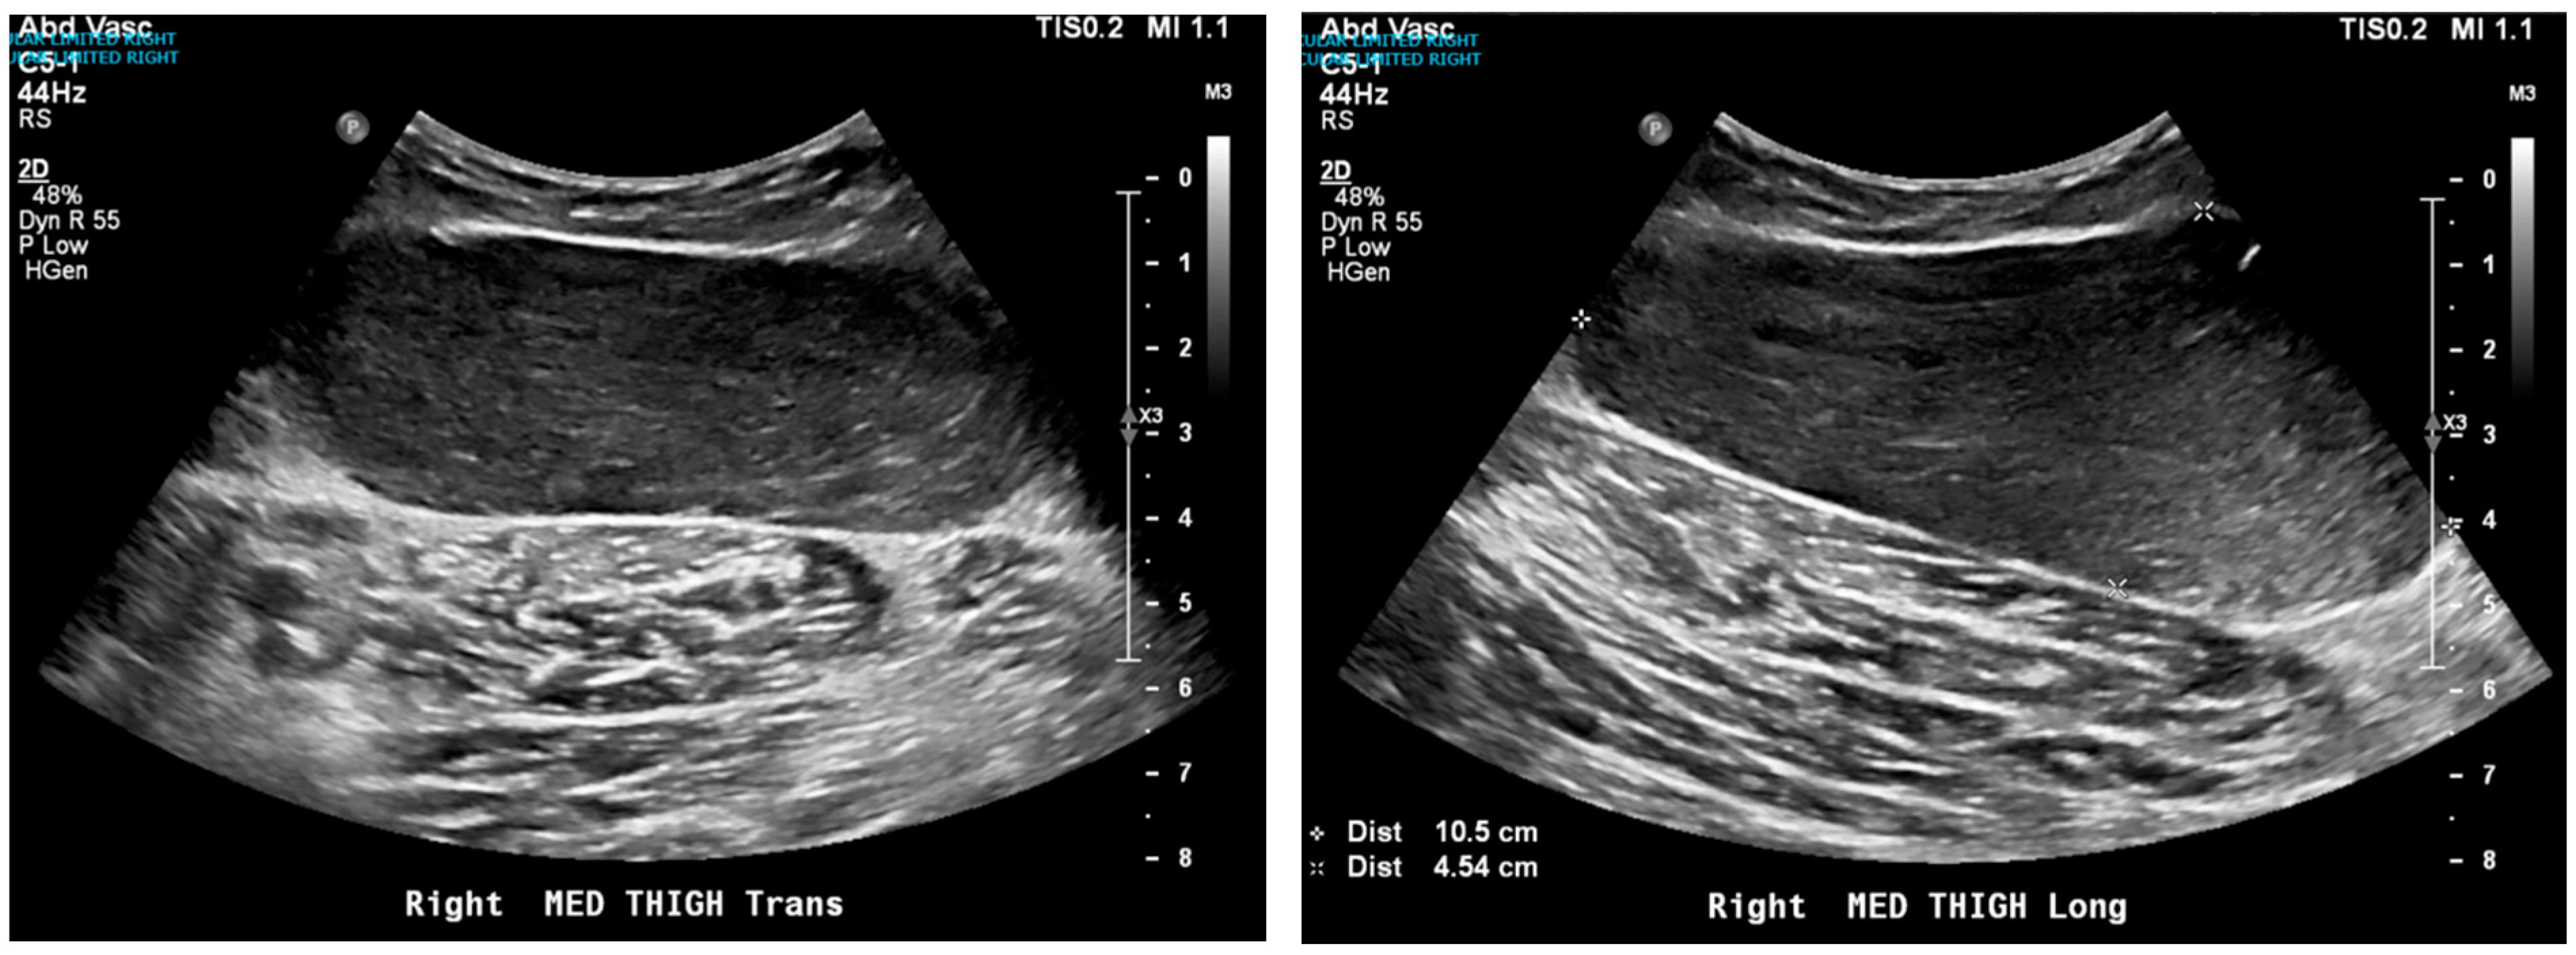

A contrast-enhanced CT scan of the abdomen and pelvis revealed an incompletely imaged, circumscribed, low-attenuation lesion within the medial aspect of the right thigh subcutaneous soft tissue measuring 7.3 × 5.6 cm (Figure 1). This was of uncertain etiology and could reflect a complex cystic lesion, thus ultrasound correlation was advised. An ultrasound of the region further characterized the lesion as a complex hypoechoic, likely solid mass, with dimensions of 10.5 cm × 4.5 cm × 9.4 cm (Figure 2). The differential diagnosis at this point included a neoplasm, though a benign process could not be excluded.

Figure 2. Ultrasound showing complex hypoechoic likely solid mass in the upper anteromedial soft tissues of the thigh measuring 10.5 cm × 4.5 cm × 9.4 cm. Neoplasm cannot be excluded.